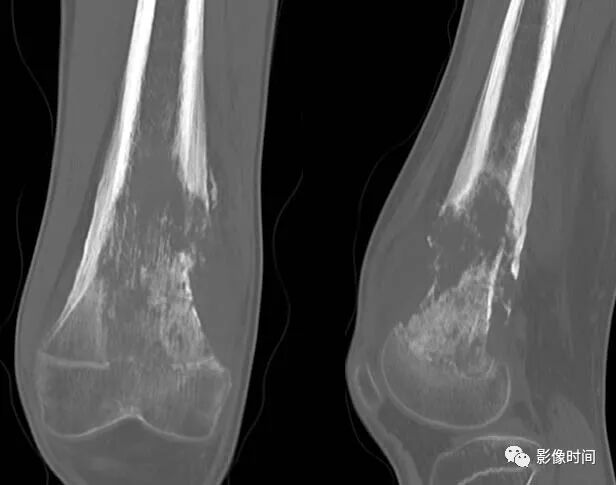

恶性瘤软骨则呈密度淡薄, 边缘模糊的不规则钙化,恶性骨肿瘤的环形钙化,最多见于软骨肉瘤(图 38),其次是骨肉瘤。CT 是发现肿瘤内软骨钙化最为敏感的检查方法。

图 38  瘤软骨钙化:软骨肉瘤